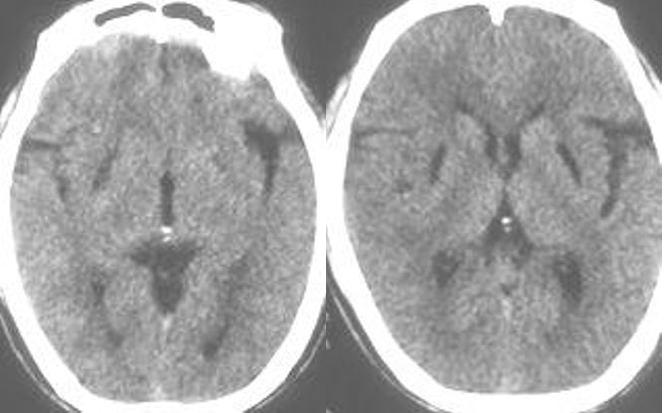

以下是引用随光逐影在2009-1-20 19:38:00的发言:[br]双侧豆状核对称性脑软化灶(中毒性脑病后遗改变?肝豆状核变性?)。

以下是引用jiangjing在2009-1-21 9:38:00的发言:[br]双侧豆状核对称性脑软化灶(中毒性脑病后遗改变?肝豆状核变性?)。